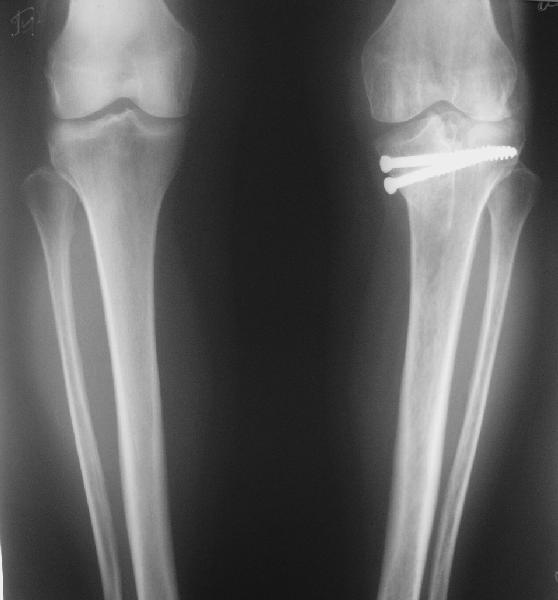

В отделение поступила пациентка из области, 68 лет. Травму получила год назад, находилась на лечении в ЦРБ по поводу перелома внутреннего мыщелка большеберцовой кости, была вот так прооперирована. На сегодняшний момент беспокоят боли в области коленного сустава при ходьбе, движения ограничены, от 180 до 100. При планировании операции возникли разногласия, на каком уровне делать остеотомию. То ли поднимать внутренний мыщелок, т.е. делать остеотомию через сустав, то ли обойтись внесуставной коррекцией оси. Второй вариант менее травматичен, но конгруэнтность сустава при этом останется нарушенной, улучшится только ось конечности. Допустима ли такая коррекция, или все-таки правильнее не менять взаимоотношения наружного мыщелка с диафизом, а поднять именно внутренний мыщелок?

Уровень остеотомии выбирали максимально высокий.В Вашем случае после удаления винтов можно было бы провести пару спиц и выбрать уровень. Нам доступны лишь Т образные пластины -имитаты АО. Очень изящно, хотя и мудрено, выглядит схема остеотомии по АО, без костной пластики.Возможно эндопротезирование и решает все проблемы разом, но мы не знаем располагает ли пациентка материальными возможностями, да и частота осложнений после ТЭП будет повыше.

Я бы остановился на подъемной косой остеотомии внутреннего мыщелка с пластикой аутокостью из крыла подвздошной кости. Фиксацию можно провести либо 4 мм Х 50 мм спонгиозными винтами наискось внесуставно (если удасться сохранить связь поднятого фрагмента с материнской костью в среднем отделе сустава , либо имплантировал опорную пластину.